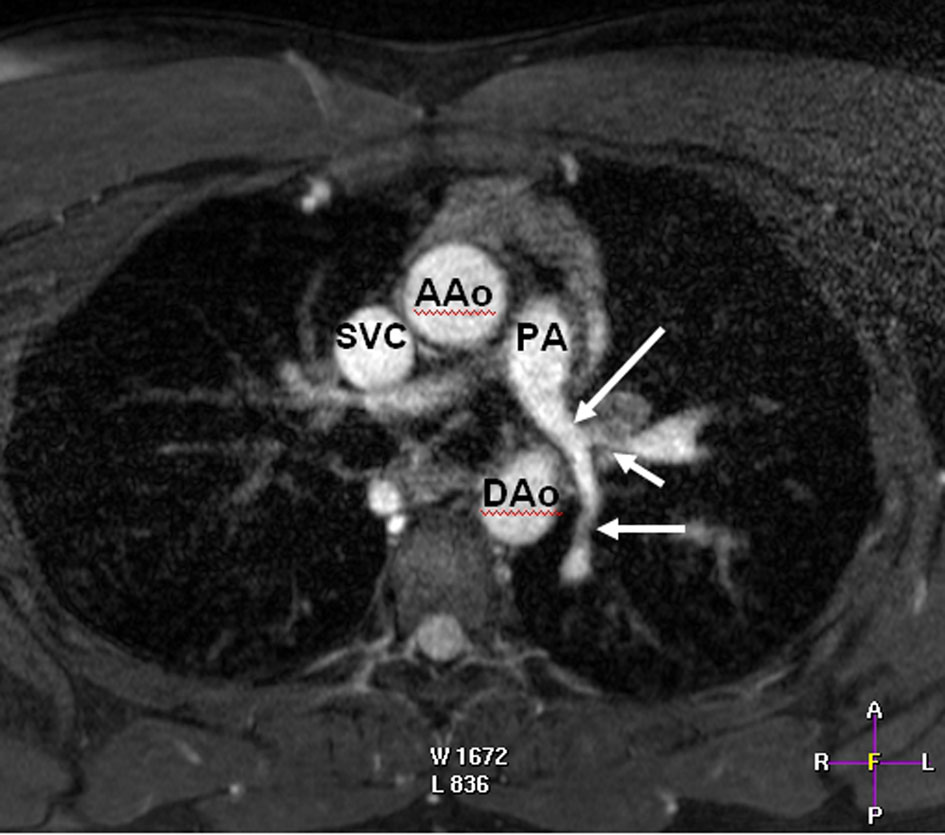

We present a case of a 28 years old male with delayed diagnosis of a severe supravalvular aortic stenosis accompanied with peripheral pulmonary artery stenosis and increased right ventricular pressure. The patient had been diagnosed since he was 3 years old to suffer from pulmonary artery hypertension of idiopathic origin. The diagnosis was made by tranthoracic echocardiography and magnetic resonance imaging.